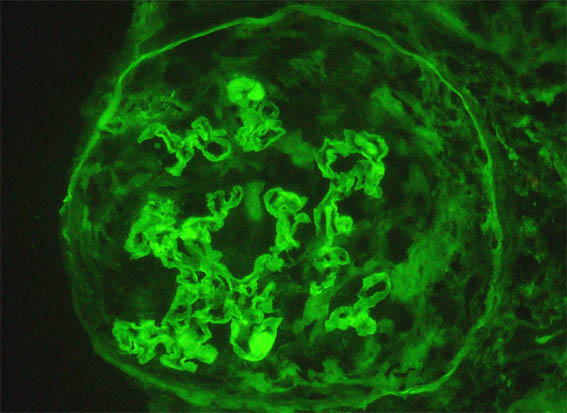

Figura 9. Inmunofluorescencia directa para IgG, X400.